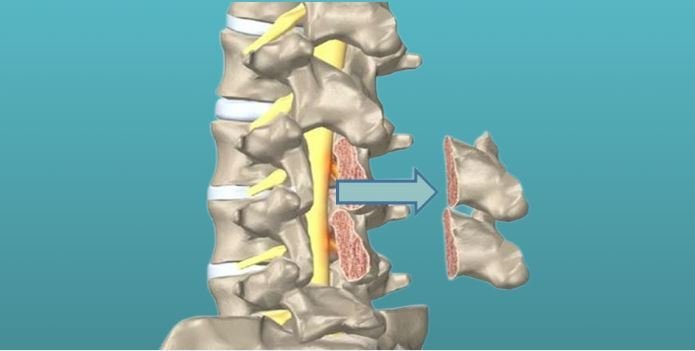

Кифопластика для восстановления позвоночника при компрессионных переломах

Компрессионный перелом позвонка вызывает сильную боль и ограничивает движения. Кифопластика — это малоинвазивный метод, который быстро снимает боль, восстанавливает высоту позвонка и возвращает к активной жизни.